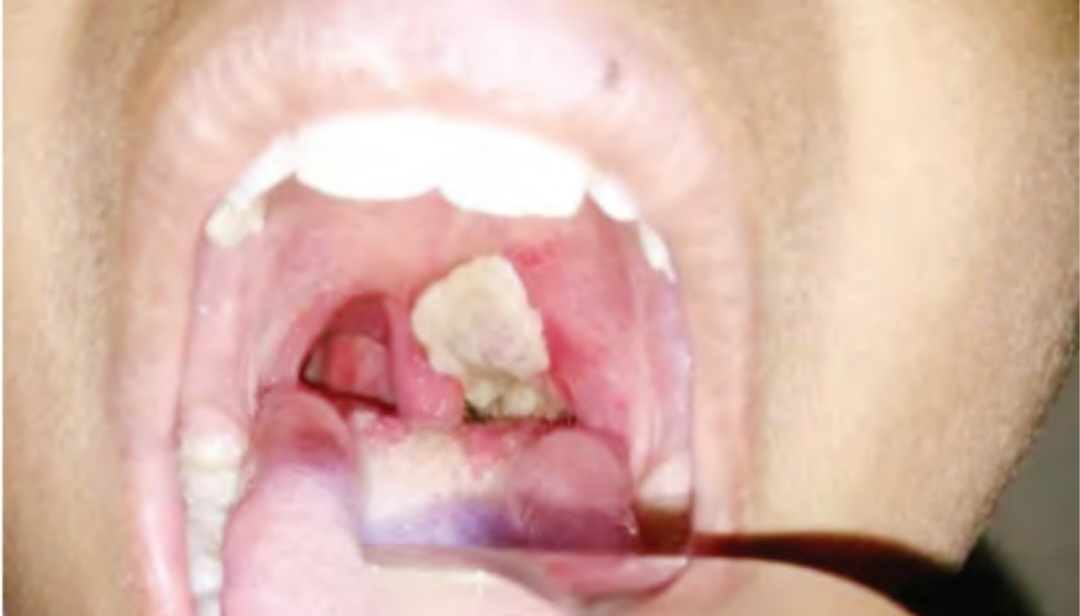

Ten children have di£d following an outbreak of diphtheria in Agaie and Bida local government areas of Niger State.

More diphtheria-related de@ths have also been reported in some communities within the two local government areas since the outbreak began.